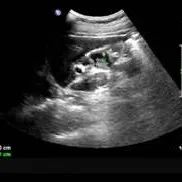

慢性胆囊炎一般是由长期存在的胆囊结石所致的胆囊慢性炎症,或急性胆囊炎反复发作迁延而来,其临床表现差异较大,可表现为无症状、反复右上腹不适或腹痛,也可出现急性发作。其典型腹部超声检查表现为胆囊壁增厚(壁厚≥3 mm)、毛糙,合并胆囊结石可表现为胆囊内强回声及后方声影。根据胆囊内是否存在结石,分成结石性胆囊炎与非结石性胆囊炎。胆囊结石分成胆固醇结石或以胆固醇为主的混合性结石和胆色素结石,中国人群中胆固醇结石占70%以上。...